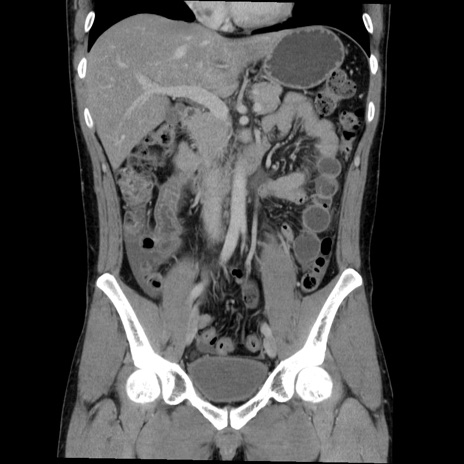

症例36(冠状断像)

【症例】20歳代 男性

【主訴】心窩部痛

【現病歴】今朝より上腹部痛あり。一旦軽快していたが再度出現したため救急要請。昨日夕に白身の魚を含む刺身を食べた。

【身体所見】BP 136/89mmHg、HR 74/min、BT 37.0℃、腹部:膨満、軟、心窩部に圧痛あり。反跳痛なし、筋性防御なし、腸雑音やや亢進あり。

【データ】WBC 17700、CRP 0.48